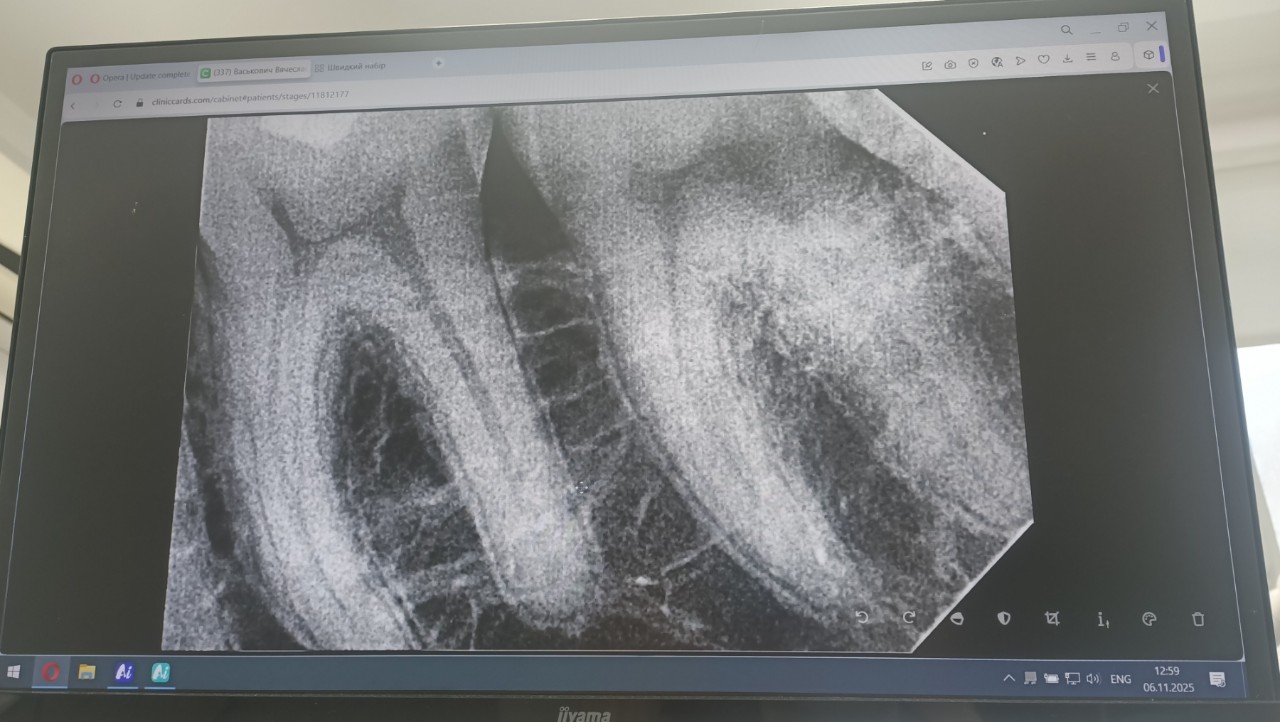

Сделал недавно снимки 6 и 7 зубов (пломбированные), прилагаю.